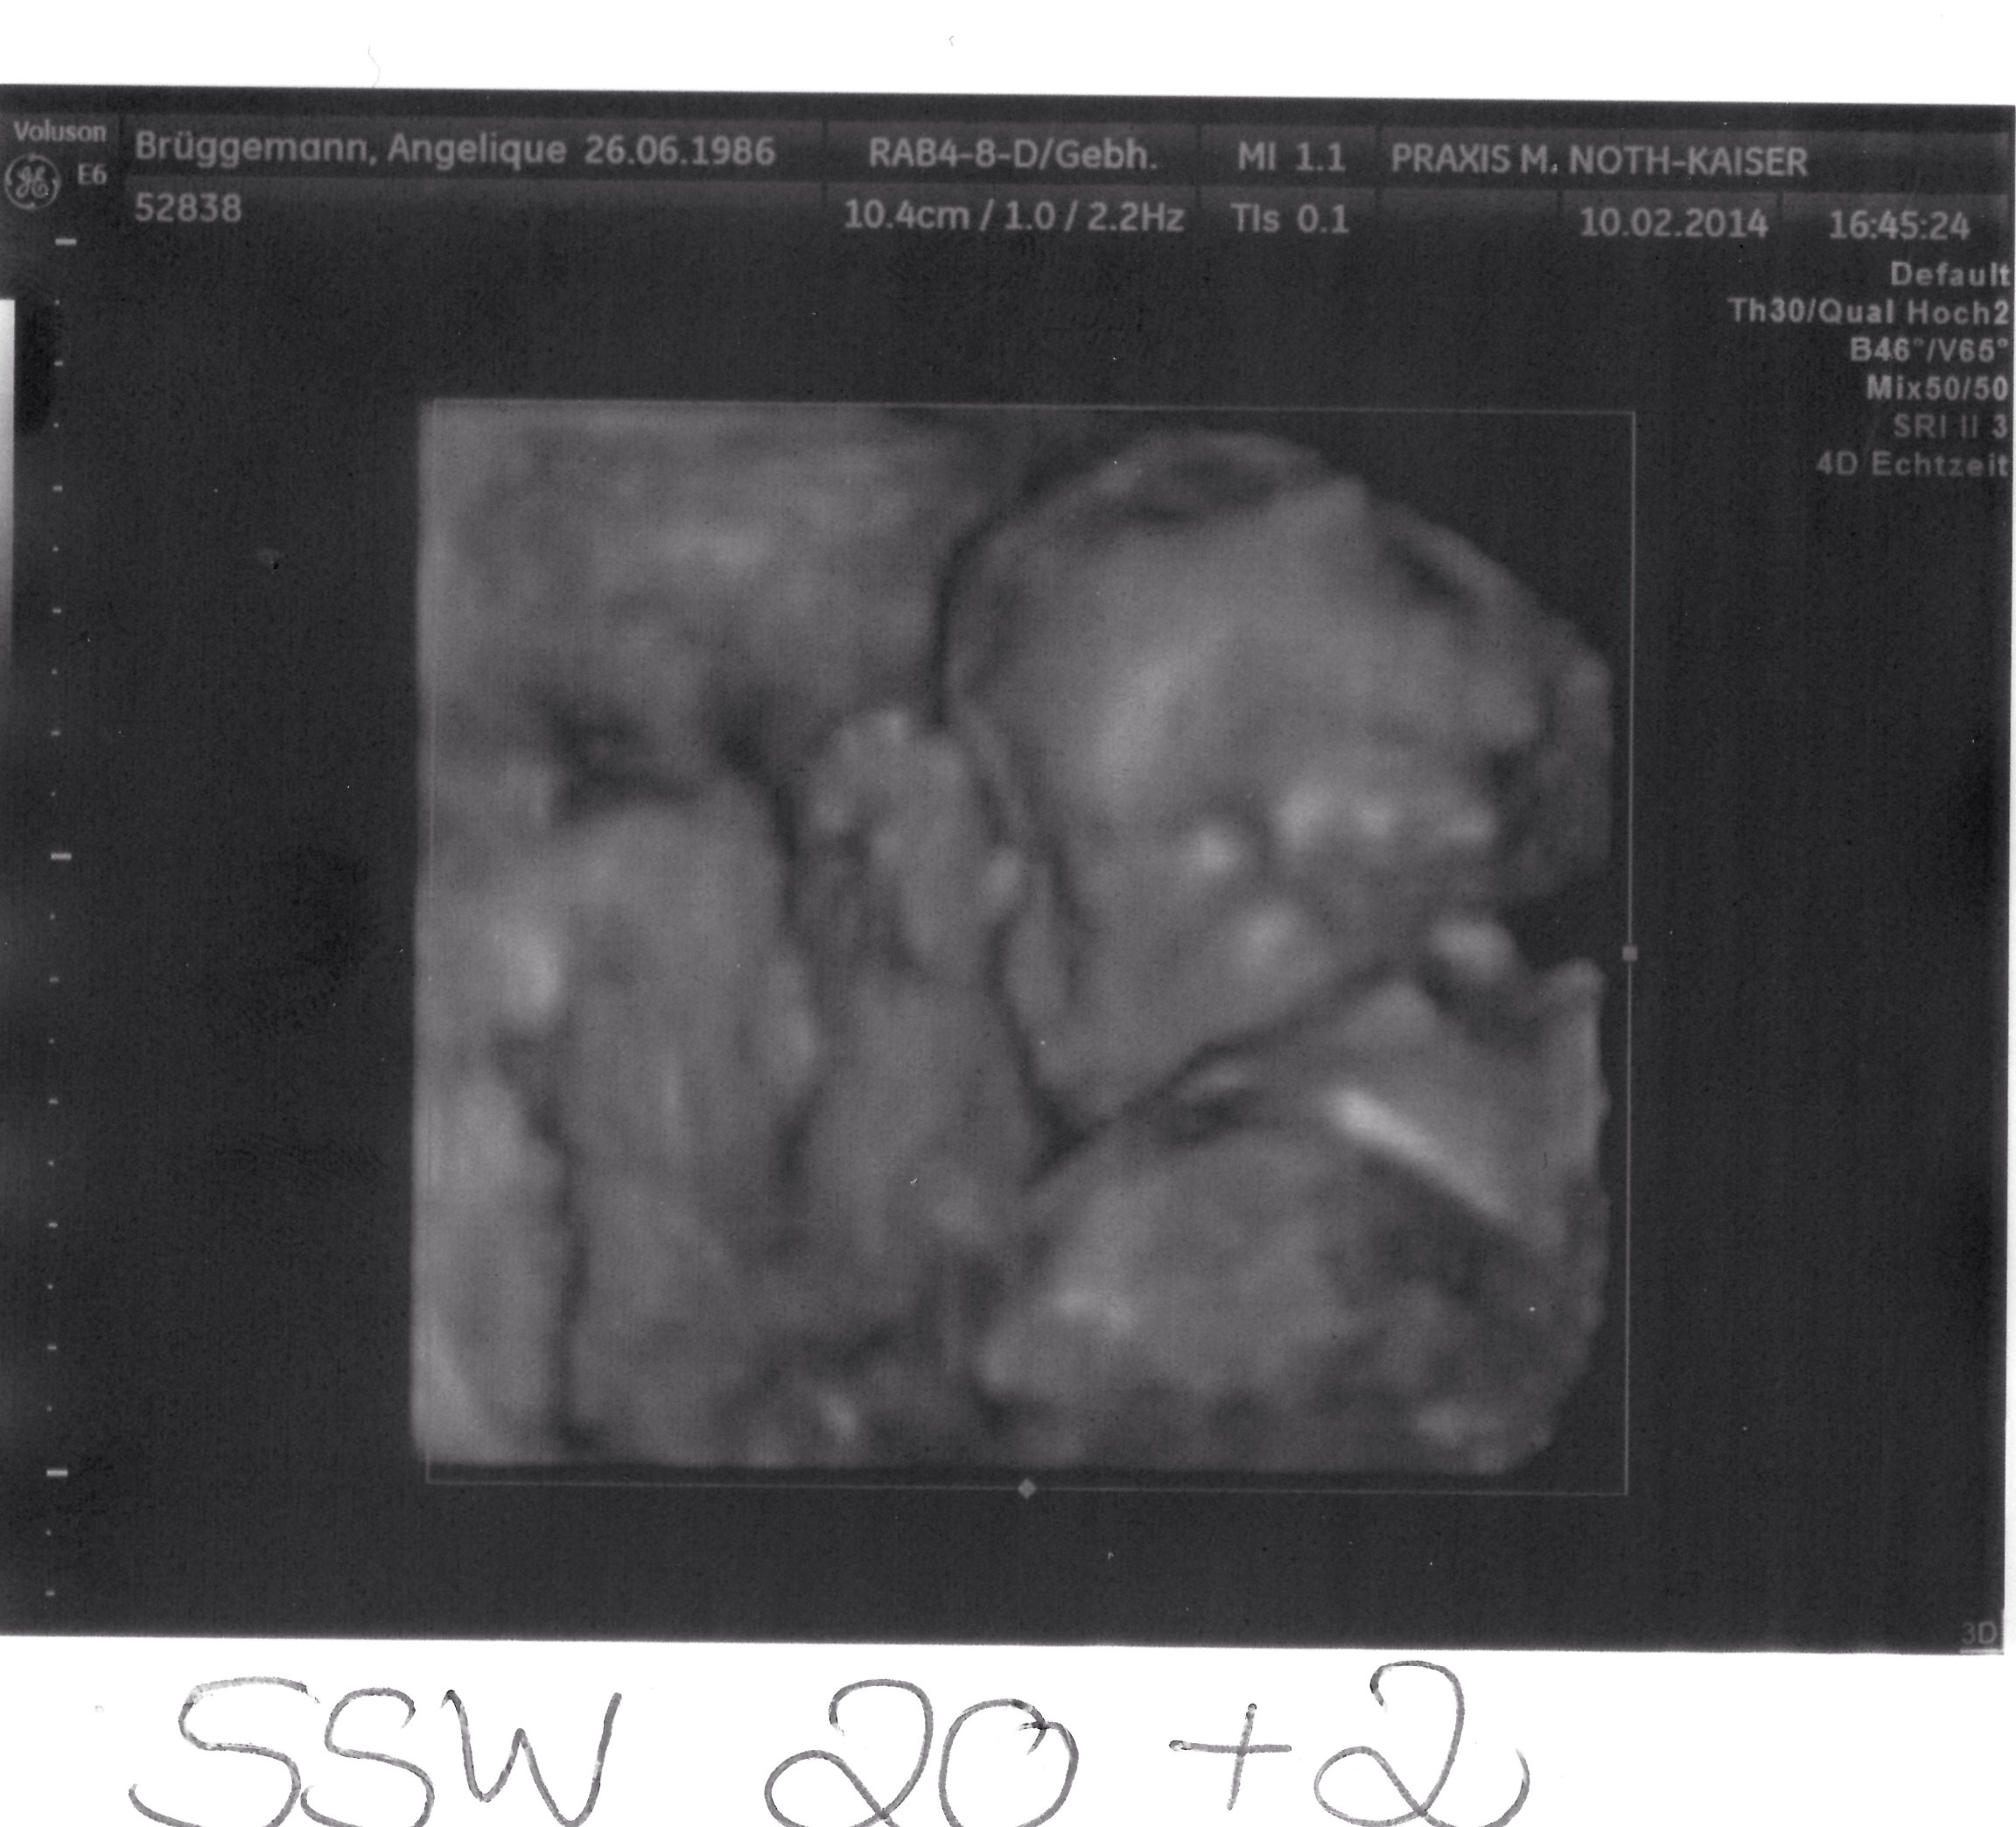

Hier das Bildchen

Ente 20+2

Ich finds so faszinierend, dass man schon so gute Gesichtszüge erkennen kann o.o Habts ihr schon an Namen gedacht? :)

Ja 3D-Bilder sind echt toll...Ente war schön am schlafen...